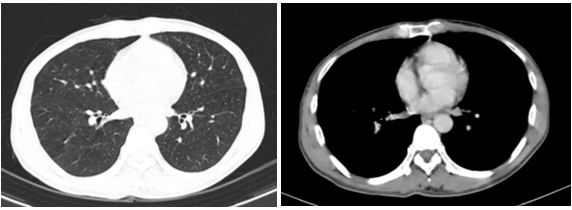

- Chụp cắt lớp vi tính lồng ngực:

Hình 2: Hình ảnh chụp cắt lớp vi tính lồng ngực chưa phát hiện tổn thương nghi ngờ thứ phát

Chụp cắt lớp vi tính ổ bụng sau mổ:

Hình 3: Hình ảnh tụ dịch vị trí diện cắt gan trái sau phẫu thuật (mũi tên đỏ) trên phim chụp CT ổ bụng